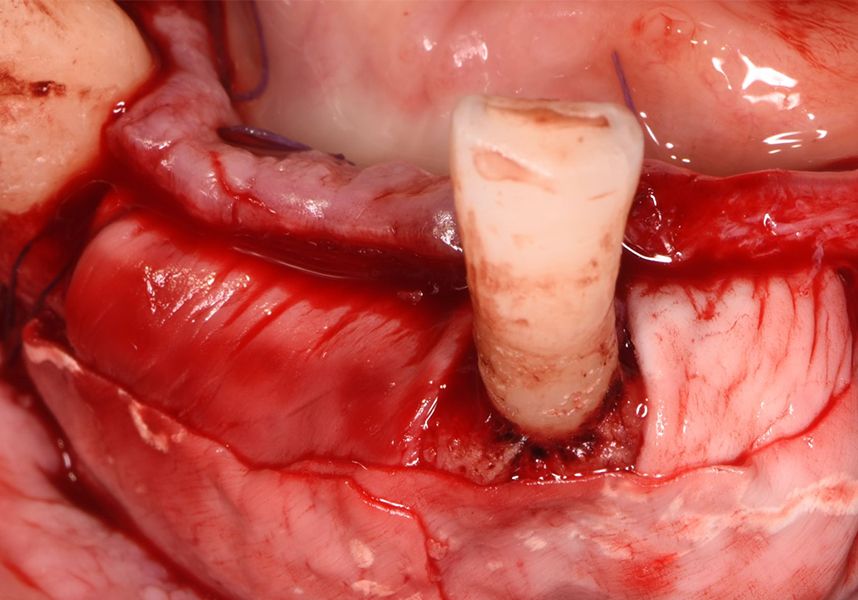

In the posterior sector three Biomimetic Ocean IC implants of 4.0x10 were inserted in positions 36, 34 and 46 with delayed load. A small regeneration was also carried out with autologous bone in the implant in position 34, where there was no exposure, but the vestibular cortical was very fine after implant insertion.

After a post-operative period without complications, the healing abutments were fitted in a second surgical stage 5 months later. Six months after implant placement, the final metal-ceramic prosthetic restoration was loaded.